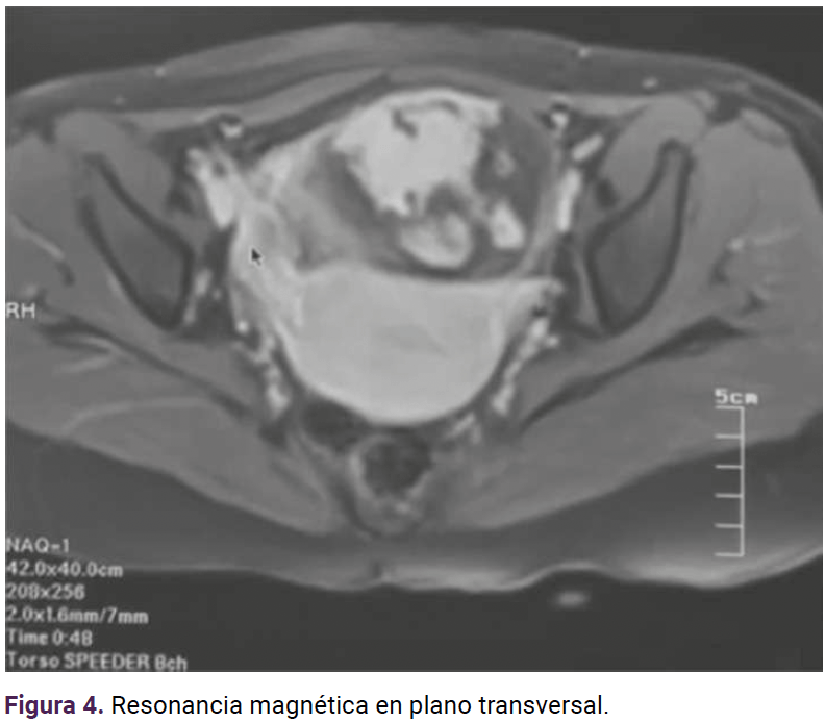

Paciente de 23 años, con antecedente de tres partos que finalizaron sin complicaciones. A las 17 semanas, del cuarto embarazo, determinadas por fecha de la última menstruación, tuvo sangrado transvaginal escaso, de aproximadamente 1 semana de evolución, dolor abdominal en el hipogastrio, de tipo cólico, con intensidad 3-10 en la escala visual análoga, sin irradiaciones, ni atenuantes o agravantes. En la exploración física se encontró con peso de 67 kg, talla 1.58 m, índice de masa corporal 26.9 kg/m , consciente, orientada, leve palidez de tegumentos, subhidratada, temperatura de 36.5 °C. Sin aparentes alteraciones cardiopulmonares, con tensión arterial de 120-80 mmHg, frecuencia cardiaca de 81 lpm, frecuencia respiratoria de 21 rpm, saturación de oxígeno 98%, sin oxígeno suplementario, abdomen blando, depresible, ligero dolor a la palpación profunda. Se palpó una masa fija, dolorosa, en la región de la fosa iliaca derecha, de aproximadamente 10 x 8 cm. El fondo uterino no fue palpable, con signo de rebote negativo. A la inspección, los genitales se advirtieron con sangrado transvaginal escaso, no activo. Al tacto vaginal el cuello uterino posterior se encontró blando, cerrado, con signo de Kennedy negativo. Las extremidades se encontraron íntegras, simétricas, con llenado capilar inmediato, sin edema. En el rastreo ultrasonográfico (Figuras 1 y 2) el útero se apreció en retroversoflexión de 7 x 4 cm, eco endometrial lineal de 6 mm. El tejido placentario se encontró con implantación aparente en el repliegue vesicouterino. No fue posible valorar la adherencia a otras estructuras. Se trataba de una gestación única, extrauterina, sin frecuencia cardiaca, con pérdida de actitud fetal, fetometría no valorable, de 15 semanas de gestación, aproximadamente, por diámetro biparietal, sin líquido libre en la cavidad. Los estudios de laboratorio a su ingreso se reportan en el Cuadro 1.

<strong>Figura 2</strong>

Figura 2. Ultrasonido transvaginal en donde se observa el embarazo ovárico en el lado derecho, con estructuras fetales dentro del ovario.

Si bien el ultrasonido transvaginal es un método auxiliar simple y reproducible para diagnosticar el embarazo ectópico, se menciona que el índice de diagnóstico acertado preoperatorio del embarazo ovárico con este método es solo del 18%.7 Algunos estudios reportan la utilidad de la resonancia magnética cuando los informes del ultrasonido transvaginal son insuficientes o inconclusos, sobre todo para diagnósticos específicos de embarazos ectópicos infrecuentes o complicados.11 Los hallazgos incluyen: estructuras parecidas a un saco gestacional, hematoma anexial o abdominal, dilatación tubárica debida a hemosalpix y realce de la pared tubárica.11 Cuando se carece de este recurso y no se consigue delimitar adecuadamente la localización precisa del embarazo extrauterino, lo conducente es la resonancia magnética.11